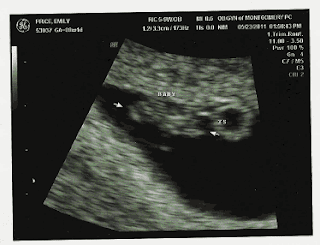

Anyway, I finally made it through the week, and Monday (yesterday) rolled around. Jordan went with me to my appointment, and thankfully, they called me back just a few minutes after we arrived. The technician got me set up for the ultrasound, and as soon as she began it, we saw the little "blob".

There really is another baby in my belly. I told the technician how I had been feeling that there were twins, so she looked around really good to make sure there wasn't another one hiding somewhere, but there's only one, which is fine with me. (I think the reason I had twins on my mind so strongly is because one of my favorite blogs that I follow, In This Wonderful Life, is written by a woman named Megan (whom I don't personally know... I just came across her blog one day and got hooked) who has PCOS like me. She is currently pregnant with twins - a boy and a girl -, and I check her blog every day for the latest updates on her pregnancy.) Anyway, the technician took measurements of my baby, and determined that he/she measured a week less than what I was estimated to be at. So, instead of being 8 weeks and 2 days pregnant today, I am 7 weeks and 2 days pregnant. I was kinda bummed about that too, but it's really no big deal at all - just means I have a week longer to go than we first estimated. It also bumped my due date back a week. My original estimated due date was January 1, 2012 - New Year's Day. Pretty cool. My due date now, however, is January 8, 2012, which is only two days after Jordan's birthday. He's really hoping the baby will be born on his birthday. We'll see how that goes. My favorite part of the ultrasound was seeing and hearing the baby's heart beat. It was nice and strong at 133 beats per minute. The technician said that, so far, everything looks great.